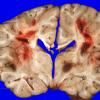

NEOPLASMS (HEMATOLYMPHOID)

Granulocytic Sarcoma (3)